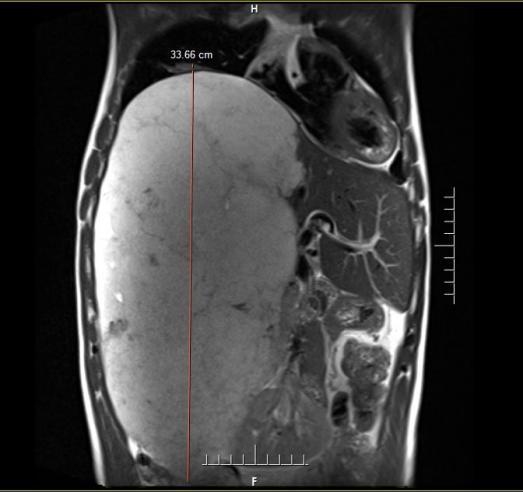

近段时间,李先生因上腹持续不适前往中国科大附一院就诊。全面的影像学检查结果让他和家人震惊不已——腹腔里竟然长了一个巨大的占位性病灶,纵向直径约34厘米,从上腹一直延伸至盆腔,如同怀胎十月的胎儿般占据了腹腔大量空间,最终确诊为“肝脏巨大占位(肝血管瘤可能)”。

“如此巨大的肝血管瘤在临床上极为罕见,更危险的是它紧贴重要血管以及肝脏胆道等器官组织,甚至将右侧肾脏挤压到了左侧。”接诊的中国科大附一院副院长、普外科肝胆外科主任医师尹大龙介绍。

经过6小时的紧张手术,纵向直径达34厘米、从腹腔延伸至盆腔的巨大瘤体被完整剥离。术中切下的瘤体重量超过3.7公斤,堪比足月新生儿,临床极为罕见。